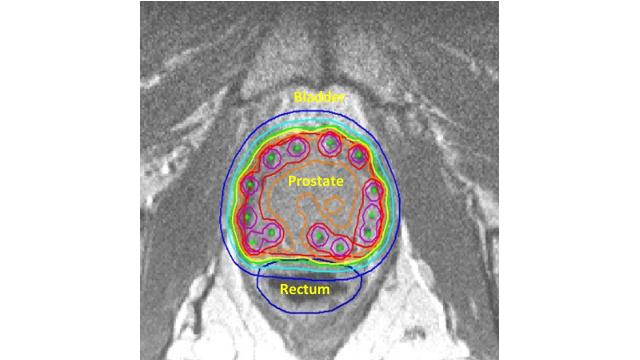

Figure 2. A scan showing the position of radioactive seeds in the prosate gland during brachytherapy for prostate cancer.

Radiotherapy can also be delivered to the body internally. This can be done by implanting radioactive sources into the body in a treatment known as brachytherapy. This is a particularly effective form of treatment for some prostate cancer patients. Figure 2 shows the position of radioactive seeds (green) into the prostate gland with bladder and rectum being exposed to low levels of radiation (light blue line).